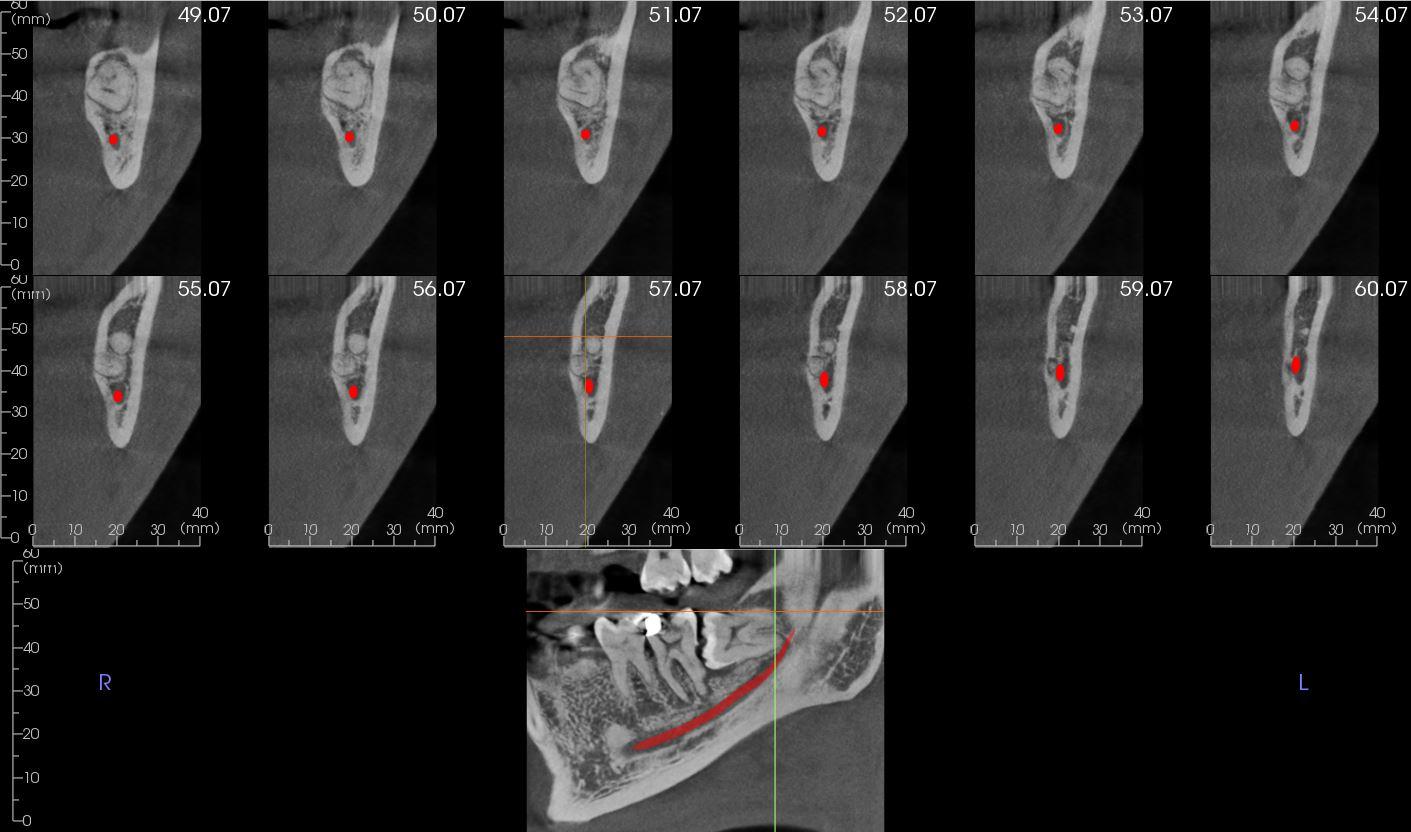

Reconstructed panoramic view and cross sections showing the

relationship of the mesial root apex of the LL8 to the IDN.